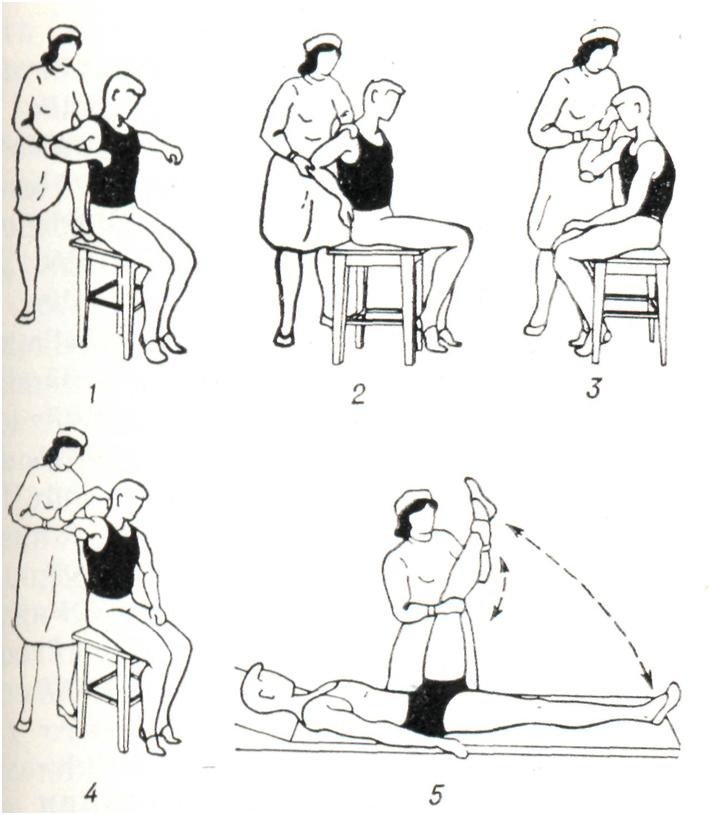

В подостром периоде используют активные, преимущественно облегченные, элементарные упражнения по основным осям движений в суставах в сочетании с общеукрепляющими и дыхательными упражнениями с постепенно возрастающей нагрузкой в положении лежа, а затем сидя и стоя. Наряду с активными упражнениями используют осторожные пассивные движения при возможно более полном расслаблении упражняемой конечности, считаясь с болевыми ощущениями (рис. 10).

В терапии хронических артритов лечебная физкультура занимает важное место в клинической, в поликлинической и санаторно-курортной практике. При поражении суставов верхних конечностей упражнения выполняют преимущественно в положении сидя и стоя (рис. 11). При патологии суставов нижних конечностей в положении лежа, сидя и стоя тренируют опорную функцию ног (рис. 12). При заболеваниях позвоночника рекомендуют также и разгрузочные для позвоночника положения, например на четвереньках (рис. 13). Применяют упражнения активные: свободные, с усилием, с широким использованием различных снарядов, предметов и специальных приспособлений (особенно для восстановления функции кисти, в целях бытовой и трудовой реабилитации и так далее). Дополнительно используют упражнения на механотерапевтических аппаратах. Больным рекомендуется выполнение самостоятельных занятий с повторением заданий в течение дня до 4—6 раз продолжительностью по 5 — 7 мин. в целях тренировки пораженных суставов. Кроме того, полезна утренняя гигиеническая гимнастика, прогулки. Целесообразно лечебную физкультуру проводить в сочетании с массажем, бальнео- и грязелечением.